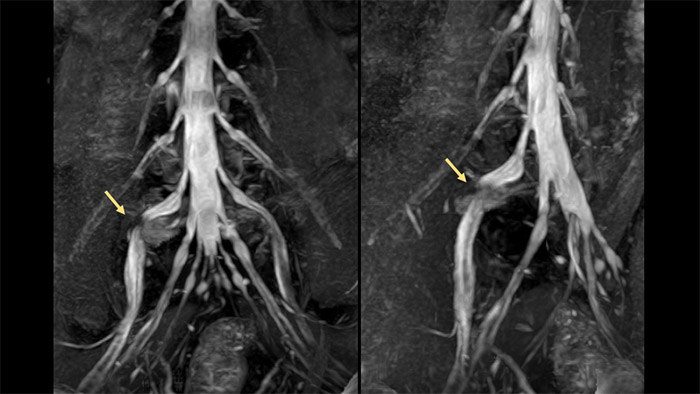

Examples of standardized tissue sodium content map and MRI lymphangiography and maximum intensity projection reconstruction.

Example of standardized tissue sodium content map (left) and example of MR lymphangiography and maximum intensity projection (MIP) reconstruction (right).